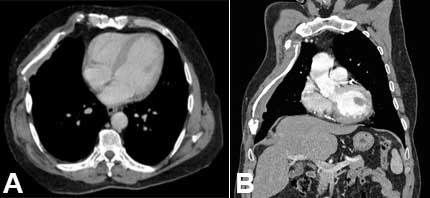

Considering the tumor histological type, the disease-free resection margins, and the good clinical progression of the patient, regular surveillance without the requirement for additional treatments was decided at a multidisciplinary team meeting. At the 1.5-year follow-up visit, physical examination and thoracic CT scan showed no evidence of tumoral recurrence (Figure 7).